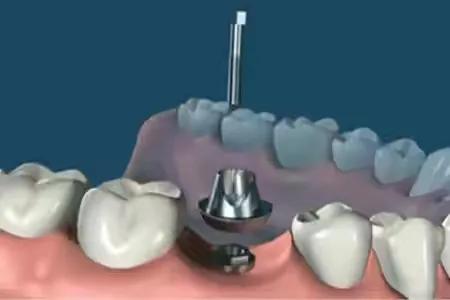

step4.

安装愈合基台,使种植体穿出牙龈,等待软组织成形。

step5.

在差不多2--3周后,软组织成形后。种植牙医生会用永久基台换下愈合基台。